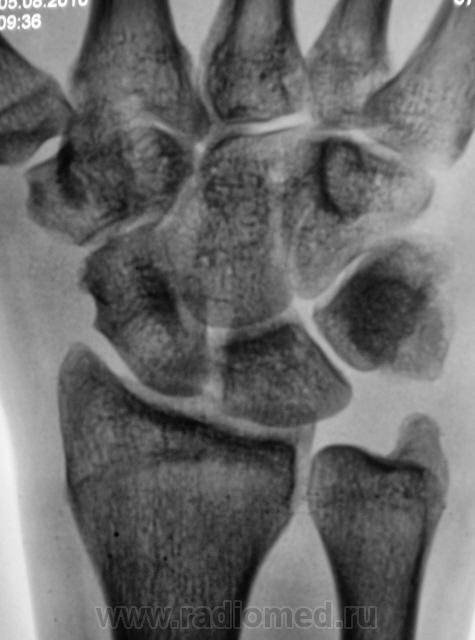

Травма месяц тому, но за помощью не обращадся. Беспокоят боли, сегодня направлен на рентгенографию лучезапястного сустава.

Перелом эпифиза луча. Не уверен насчет шилов. отростка локтевой кости. Регионарный остеопороз.

А, что за выемка по контуру ладьевидной?

Вариант основания бугорка, как бы "талия"...как по мне. И вообще - переломы в обозримом прошлом сомнительны....

Думаю, была сломана и не срослась полулунная кость. Сколько лет больному и чем он занимается по жизни?